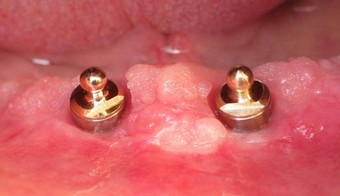

Próteses móveis sobre Implantes

Soluções protéticas móveis estabilizadas sobre implantes.

Prótese móvel estabilizada por sistema de bola.

Prótese móvel estabilizada por sistema de barra.